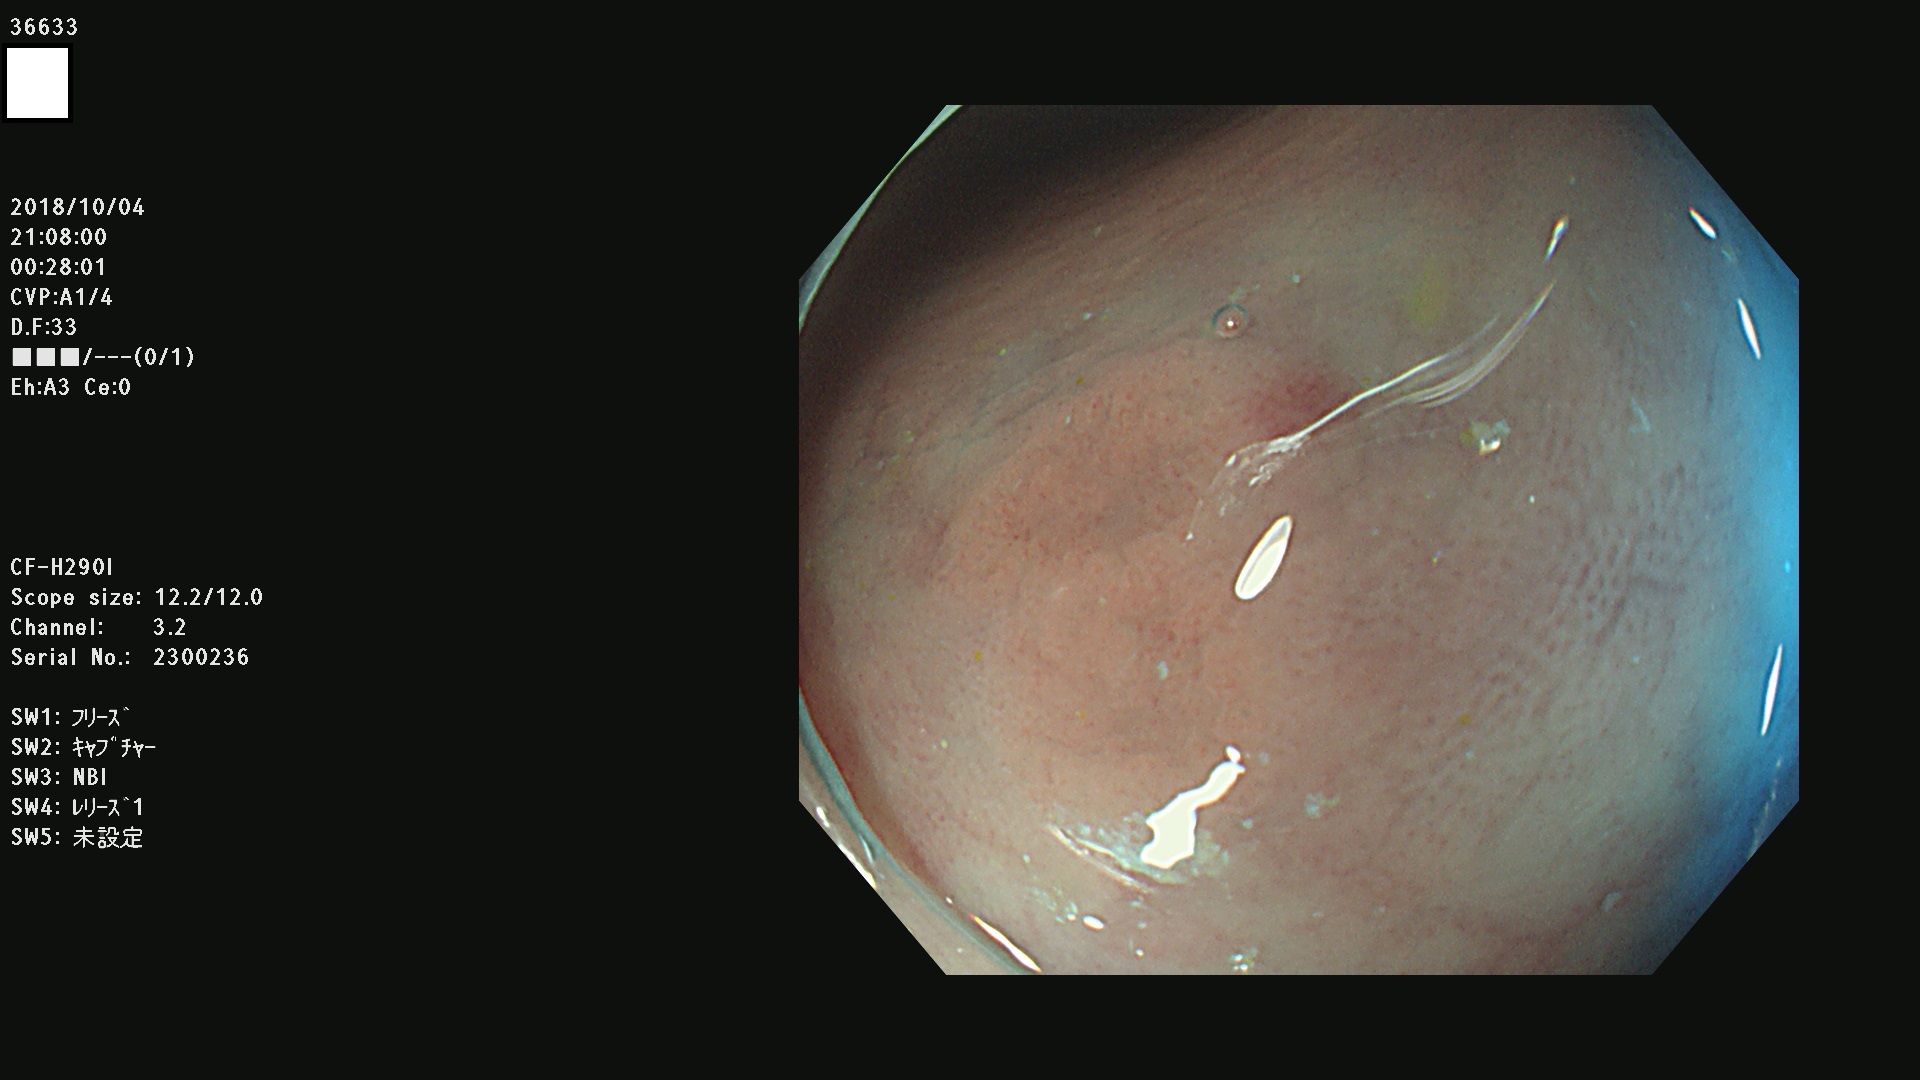

36600 36601 36603 36605 36606 36608 36609 36610 36611 36612 36613 36615 36617 36620 36621 36624 36625 36626 36627 36628 36629 36631(SSAPのみ) 36632 36633 36634 36636(SSAPのみ) 36637(SSAPのみ) 36639 36640 36642 36643 36644 36646 36647 36648 36649(SSAPのみ) 36650(SSAPのみ) 36652 36653 36654 36655(SSAPのみ) 36656 36657 36658 36659 36660 36661(SSAPのみ) 36665 36668 36669 36672 36673 36676 36677 36678 36679 36681 36682 36683 36684 36685 36687(SSAPのみ) 36691 36692 36693 36694 36695 36696 36697 36699(SSAPのみ)